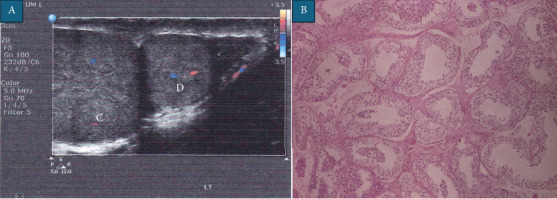

Polyorchidism, or supernumerary testes (SNTs), is a rare congenital condition, management of which remains debated, particularly in paediatric cases with other concomitant features. We report a case of intrascrotal polyorchidism in a 14-year-old boy managed surgically due to parental preference and the need for histological confirmation. The patient presented with a 2-week history of painless heaviness in the scrotum. Physical examination and Doppler ultrasonography revealed a 1.8 cm mass fused to the inferior pole of the left testicle with associated Grade 1 varicocele, hydrocele and testicular appendix. Although MRI of the scrotum was initially offered, the family declined in favour of timely histological confirmation. Surgical exploration confirmed a fused supernumerary testicle and a biopsy showed normal spermatogenesis; this was consistent with Type A3 triorchidism. The patient had no complications or recurrence of symptoms at 12-month follow-up. This case highlights the use of surgical exploration in selected intrascrotal polyorchidism cases where imaging can be inconclusive or histological confirmation is required. Parental concerns and long-term reassurance may also reasonably influence management decisions.